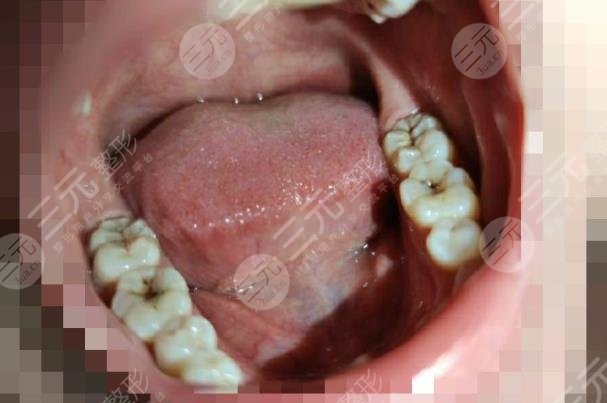

Wuhan University Stomatological Hospital found that it is really better, and the diagnosis and treatment environment is particularly comfortable, the doctor gave me a detailed examination, told me that the gums have been inflamed, let me repair in time, for my teeth to clean up before starting to repair, at the beginning of the cleaning to me used a certain amount of medicine, at that time there was not so much pain, go home to rest for about a day, and then let me go to the hospital to repair again, a total of three times, my teeth were repaired.

Now it has been almost two months since the restoration was completed, and the overall result is really clear, I didn't expect that after such a tooth restoration, eating will not be affected, and there will be no pain, I am really grateful to the doctors of Wuhan University Stomatological Hospital.